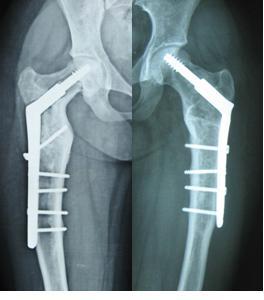

图1女性,18岁,术前肢体短缩9cm图2 术后力线纠正

图3 术后肢体等长

图4 女性,17岁,术前肢体短缩4cm图5 术后2年复查肢体等长,截骨处愈合